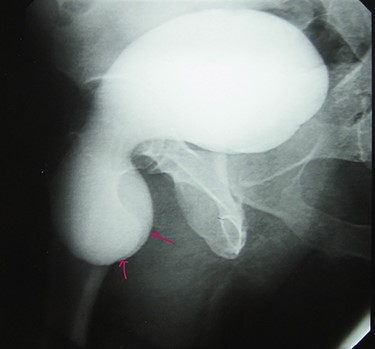

A 72-year-old man with a history of controlled diabetes and hypertension presented to our department with right inguinal swelling and intermittent lower urinary tract symptoms (LUTS) with pollakiuria, dysuria, prolonged micturition time and a sensation of a full bladder after micturition. He reported nausea, vomiting and right lower quadrant paint. The patient also reported having to manually compress the scrotum in order to empty the bladder. Physical examination revealed a slightly painful on palpation and reducible 6 cm right inguinal hernia extending into the right hemiscrotum. The body mass index of the patient was 31.4 kg/m2. His PSA was 4.3 ng/ml. On uroflowmetry, maximum flow rate (Qmax) was 13 ml/s and the voided volume was 180 cc. The uroflow curve was flat. The Bacteriological examination of urine was negative. Retrograde urethrocystography revealed right inguinal hernia containing a portion of the urinary bladder (Figs 1,2). He also had an intravenous urography in order to study the upper urinary tract and to have an idea of the renal function. This radiological exploration confirms the data of the retrograde urethrocystography and illustrates well the bladder hernia. However, a moderate left hydronephrosis with a nonobstructive pyelic calculus of 1.5 cm was observed on intravenous urography (Figs 3,4). Intraoperative findings revealed a direct right inguinal hernia with complete herniation of bladder into the scrotum. The bladder appeared healthy with no signs of injury and was restored to its normal anatomical position without resection. The hernia was repaired with a biologic mesh by the Lichtenstein technique. The patient had an uneventful postoperative course. Concerning his pyelic calculus problem, shock wave lithotripsy sessions were scheduled.

Urethrocystography: no obstruction under the bladder in the per mictional image.